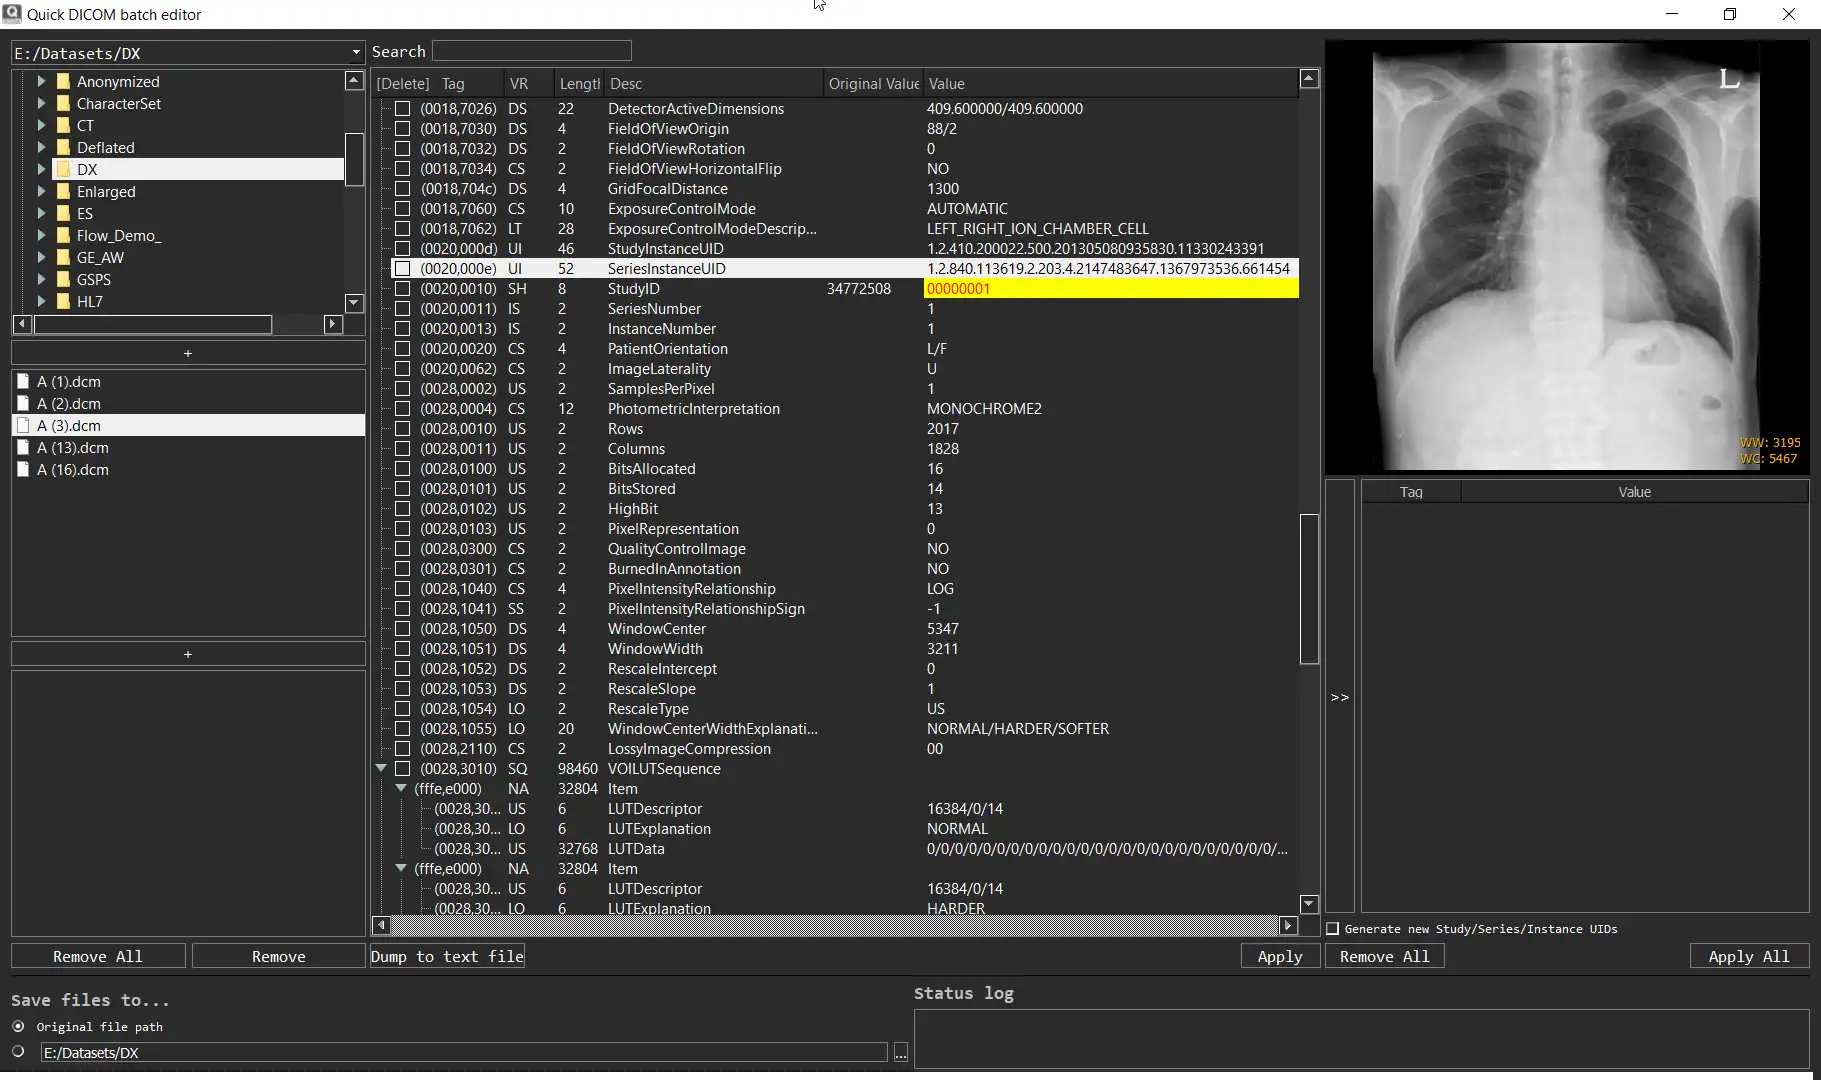

SCREENSHOTS

* Descrição geral

- Ver e modificar tags DICOM de um único arquivo

- Visualize e modifique as tags DICOM de vários arquivos

- Despeje as tags DICOM em um arquivo de texto

- Imagens de visualização (dados de pixel DICOM)

- Visualize e modifique as tags DICOM de um único arquivo

- Visualize e modifique as tags DICOM de vários arquivos

- Despejar tags DICOM em um arquivo de texto

- Imagens de visualização (dados de pixel DICOM)